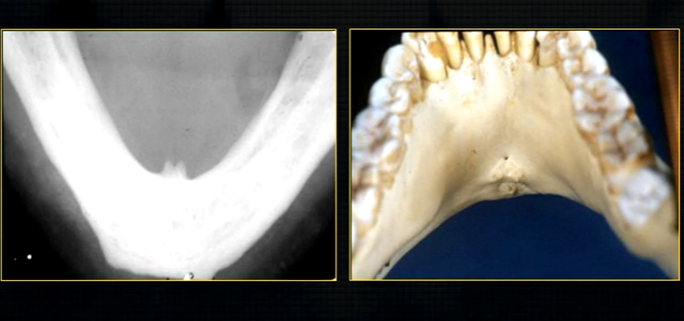

lower occlusal

small bony spurs of the genial tubercles